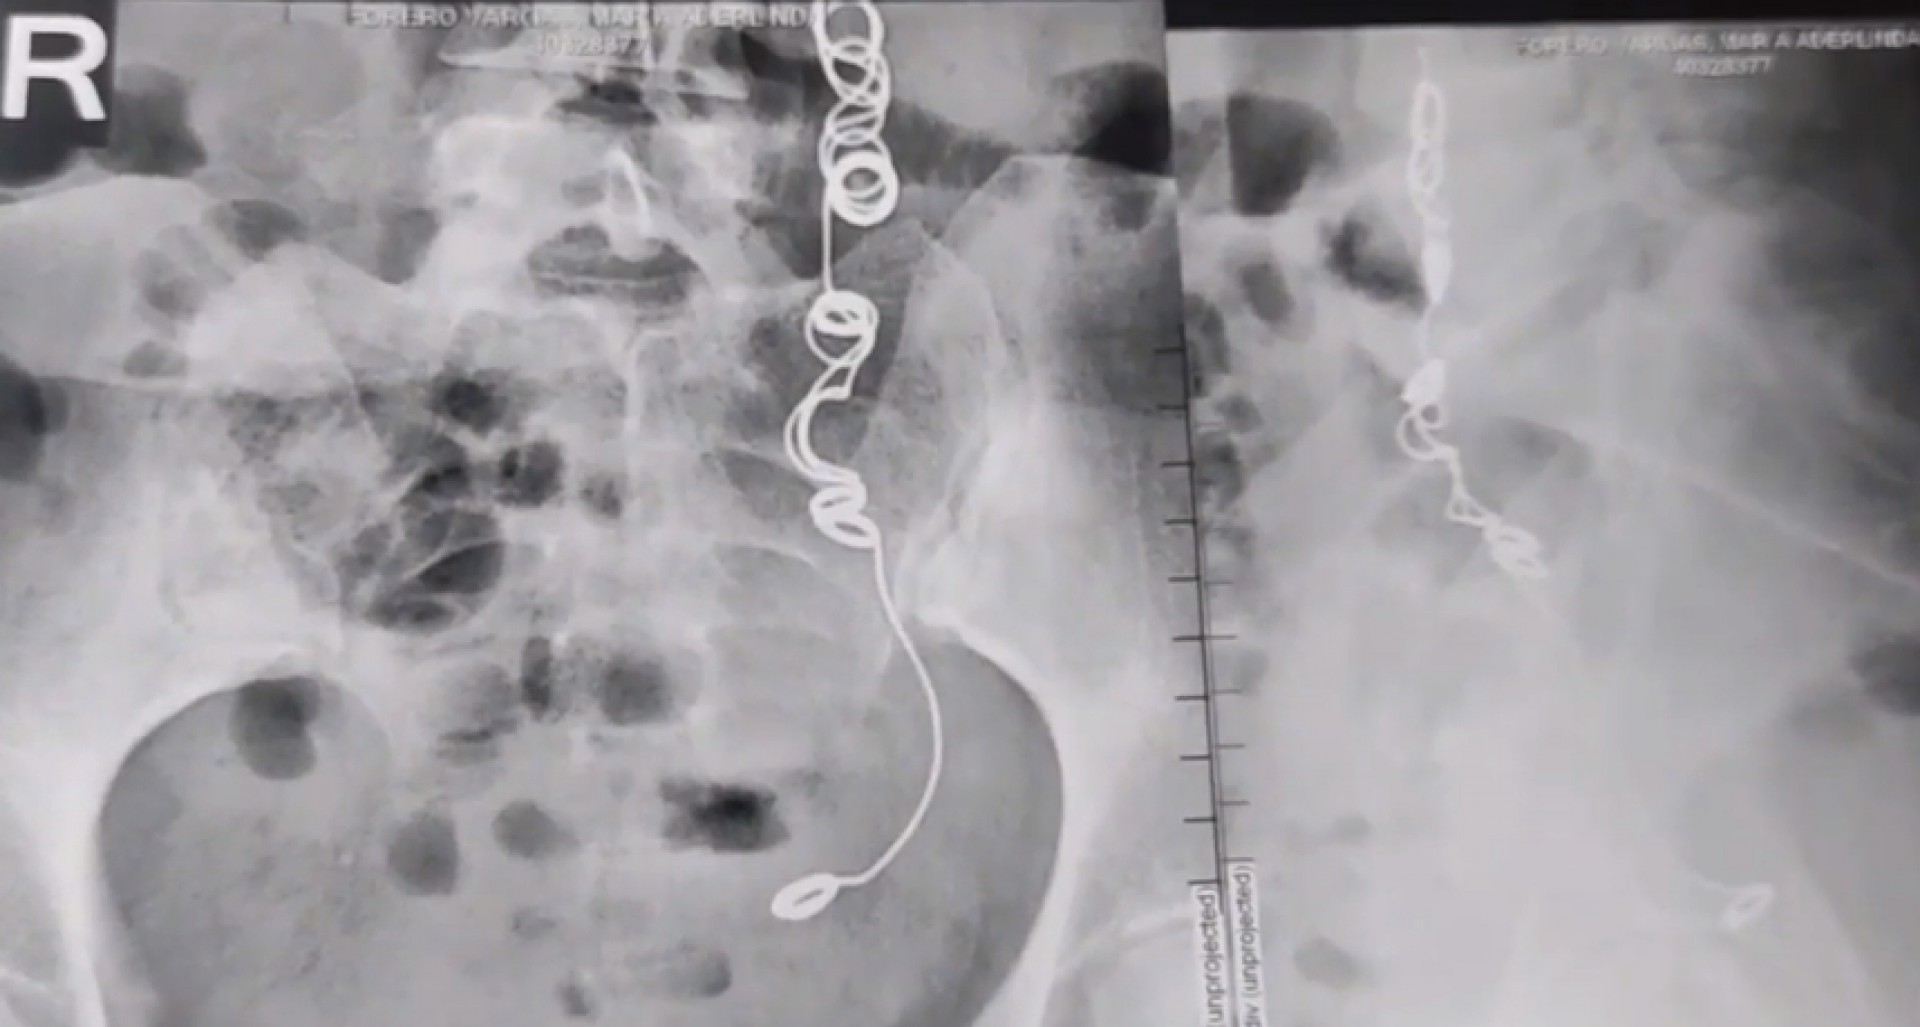

Veja foto do raio-x de mulher que descobrir agulha e linha preso dentro do próprio corpo

Colombiana que fez cirurgia em 2012 e conviveu mais de 10 anos com fortes dores no corpo descobriu uma agulha envolta de linha dentro de seu corpo

Colombiana que fez cirurgia em 2012 e conviveu mais de 10 anos com fortes dores no corpo descobriu uma agulha envolta de linha dentro de seu corpo (Foto: Reprodução/Youtube)